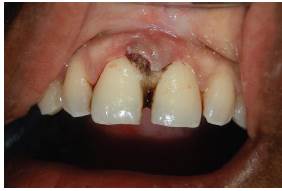

Se hace valoración clínica completa, se procede a realizar asepsia de la zona, aplicación de lidocaína al 2 % 1:80.000, mediante técnica anestésica infiltrativa se realiza incisión con hoja de bisturí número 15. Se levanta colgajo de espesor total para exponer la lesión; posteriormente aflora tejido nodular único, de consistencia firme y depresible, sangrante, doloroso a la palpación, de color rosa, de 4 mm de ancho por 9 mm de largo, de superficie lisa, base sésil. Se hace la extirpación completa de la lesión (figura 2A). Se realiza raspado y alisado radicular ultrasónico y manual. Se efectuó detoxificación de la raíz con fórmula magistral de ácido cítrico gel al 3 0% y hemostasia por dos minutos (figura 2B). Se sutura con Nylon 6-0 con puntos en ocho (figura 3A). Se realizó cita de control 8 días después de la cirugía para retirar suturas (figura 3B). Se cita nuevamente a los 15 días para realizar seguimiento. Se evidenció cicatrización de los tejidos blandos, y dos meses después se encontró un proceso de cicatrización dentro de lo esperado, sin complicación alguna.

La muestra extirpada se almacenó en formol tamponado al 10 % para su análisis histopatológico (figura 4A). Esta arrojó el siguiente resultado: los cortes mostraron mucosa oral con hiperplasia marcada del epitelio. A nivel de la lámina propia se observó infiltrado inflamatorio de predominio linfoplasmocitario de distribución heterogénea, proliferación fibrocolágena y de vasos de pequeño calibre (figura 4B) El diagnóstico definitivo es granuloma telangiectásico.